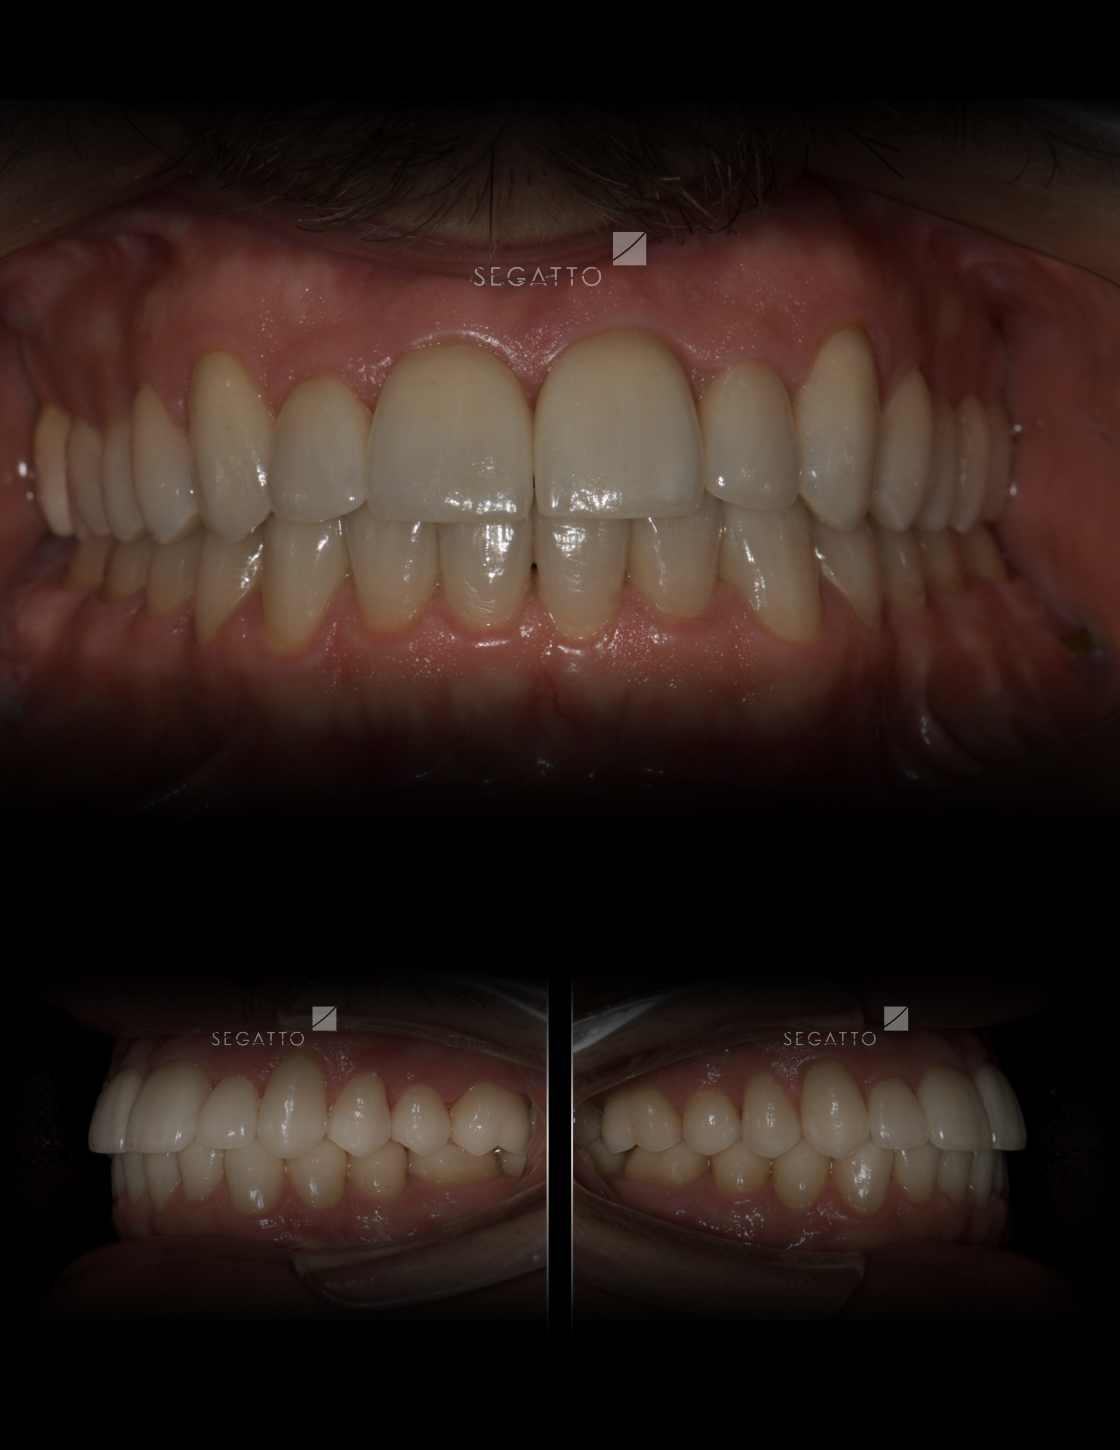

Orthodontics

Cases